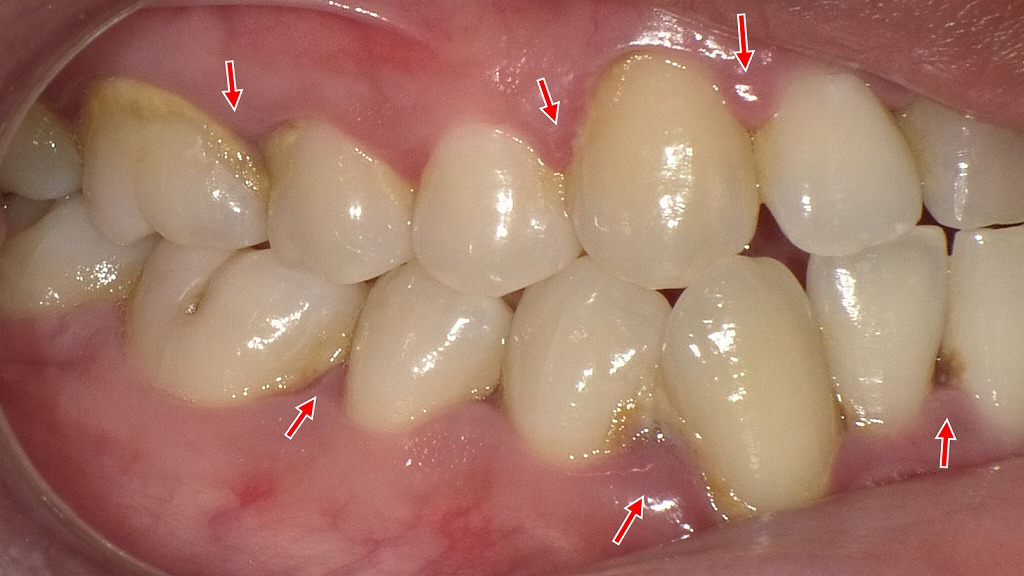

この画像は、歯の表面や歯と歯の間に黒い歯石(黒色歯石・縁上歯石)が沈着している様子を示しています。

赤い矢印の部分に注目すると、歯肉の境目や隣接面に黒〜茶色の付着物が見られます。

黒い歯石は、主に**歯肉縁下歯石(しにくえんかしせき)**と呼ばれ、歯ぐきの縁や内部にできる硬い沈着物です。

唾液中のカルシウムやリン酸が、プラーク(歯垢)に含まれる細菌と反応して石灰化したもので、時間が経つほど黒く変色します。

喫煙者や歯周病の方に特に多く見られます。

- 歯石表面はざらざらしており、細菌(プラーク)が付着しやすいため、

→ プラークの温床となり、歯周病や口臭の原因になります。 - 歯ブラシでは除去できず、放置すると炎症が進み、歯ぐきが下がったり出血しやすくなります。